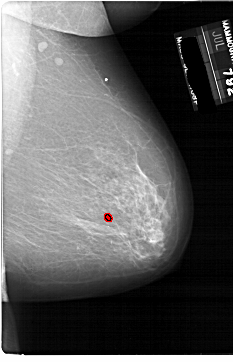

A_1861_1.RIGHT_CC

RIGHT_MLO LINES 6871 PIXELS_PER_LINE 4426 BITS_PER_PIXEL 12 RESOLUTION 43.5 OVERLAY

FILE: A_1861_1.RIGHT_CC.OVERLAY

TOTAL_ABNORMALITIES 1

ABNORMALITY 1

LESION_TYPE CALCIFICATION TYPE PLEOMORPHIC DISTRIBUTION CLUSTERED

ASSESSMENT 4

SUBTLETY 2

PATHOLOGY BENIGN

TOTAL_OUTLINES 1

BOUNDARY